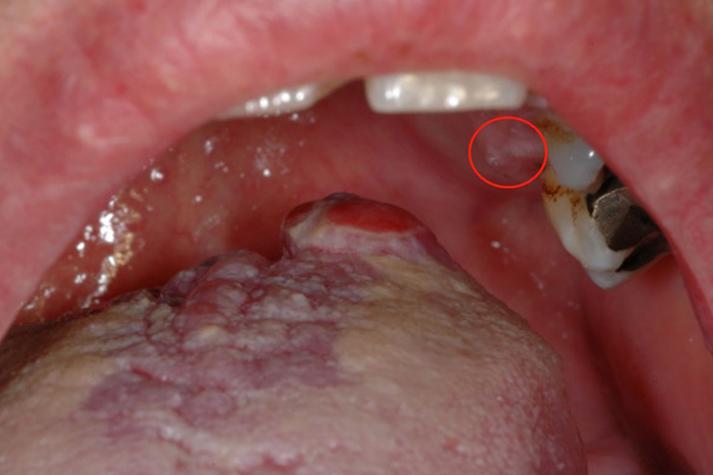

口腔尖锐湿疣初期有何不适症状? 口腔尖锐湿疣的初期症状非常不典型,甚至可能没有任何感觉,很多人在早期是完全不自知的,不能仅凭“感觉”来判断,必须结合医学检查。 以下是根据临床观察总结的口腔尖锐湿疣可能出现的初期感觉和症状,从最常见到较少见排列: 最典型的初期表现(无症状或轻微不适) 这是绝大多数患者的初期状态,病毒刚刚在口腔黏膜内...